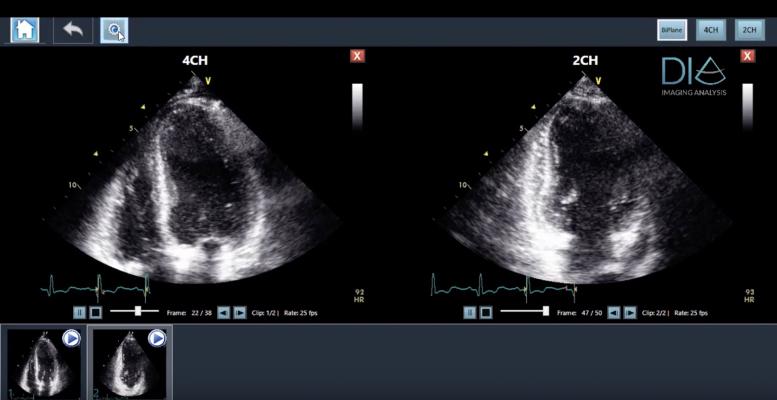

The LVivo Cardiac Toolbox, an artificial intelligence (AI)-powered solution, is designed to analyze cardiac ultrasound images automatically and objectively, to reduce the subjectivity of manual or visual analysis methods used today.

DiA's LVivo Cardiac Toolbox uses novel pattern recognition, deep learning and machine learning algorithms that automatically imitate how the human eye detects borders and motion. DiA's automated solution generates fast and accurate image analysis to support the clinician's decision-making process.

LVivo Cardiac Toolbox is vendor-neutral, supporting DICOM clips of various ultrasound systems. Konica Minolta will offer the LVivo Toolbox as a part of Exa's diagnostic-quality zero-footprint, server side rendering universal viewer for DICOM and non-DICOM images. The integration has been designed according to Exa's user interface to assure the most efficient workflow and accessibility to all Exa Cardio PACS (picture archiving and communication system) users.